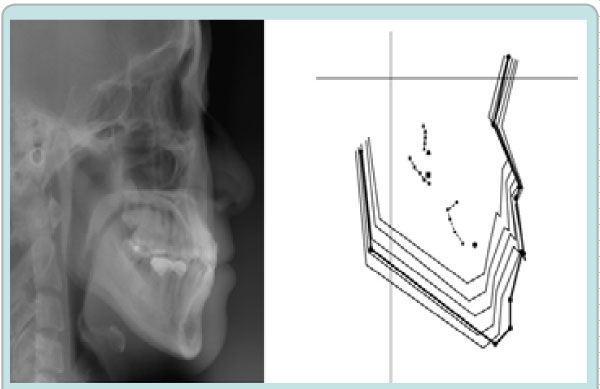

The space analysis showed 8.0 mm of space deficiency in the upper dentition and 1.5 mm space deficiency in the lower dentition. Both upper and lower dental arches were symmetric ovoid shape (Figure 1). Panoramic findings showed #13 missing and #27 elongation (Figure 2). Cephalometric analysis indicated that this patient had a skeletal Class I pattern with an ANB angle of 3.4 ° with a mean mandibular angle. The upper incisor positions showed tendency of mild retroclination measured from U-1 to A-P plane of 5.3mm. The mandibular incisors were retroclined as compared to norms. (Figure 3, Table 1).

Figure 3: Initial Cephalometric radiograph